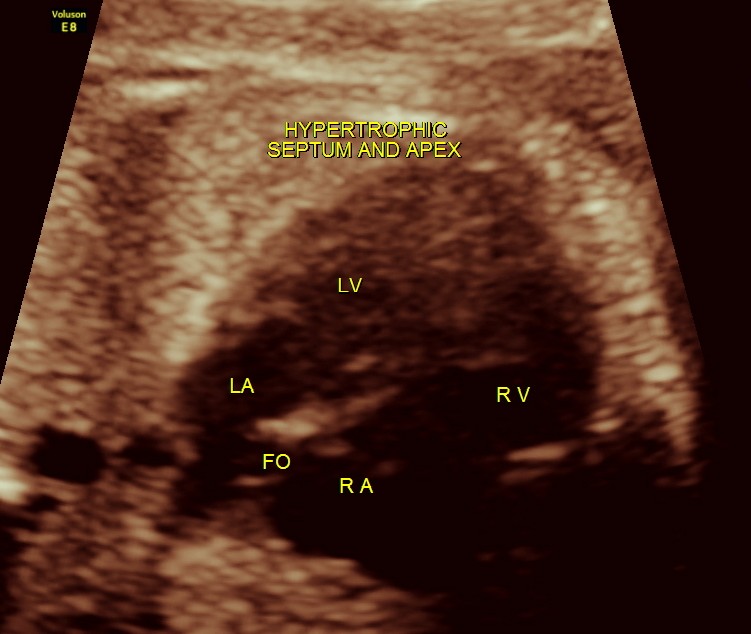

The next 2 images show the findings of the fetal heart. Significant hypertrophy of the septal and apical regions of the Left ventricle are seen.